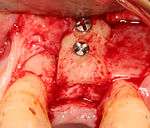

Placing the implant

Most implant systems have five basic steps for placement of each implant:[6](pp214–221)

- Soft tissue reflection: An incision is made over the crest of bone, splitting the thicker attached gingiva roughly in half so that the final implant will have a thick band of tissue around it. The edges of tissue, each referred to as a flap are pushed back to expose the bone. Flapless surgery is an alternate technique, where a small punch of tissue (the diameter of the implant) is removed for implant placement rather than raising flaps.

- Drilling at high speed: After reflecting the soft tissue, and using a surgical guide or stent as necessary, pilot holes are placed with precision drills at highly regulated speed to prevent burning or pressure necrosis of the bone.

- Drilling at low speed: The pilot hole is expanded by using progressively wider drills (typically between three and seven successive drilling steps, depending on implant width and length). Care is taken not to damage the osteoblast or bone cells by overheating. A cooling saline or water spray keeps the temperature low.

- Placement of the implant: The implant screw is placed and can be self-tapping,[18](pp100–102) otherwise the prepared site is tapped with an implant analog. It is then screwed into place with a torque controlled wrench[19] at a precise torque so as not to overload the surrounding bone (overloaded bone can die, a condition called osteonecrosis, which may lead to failure of the implant to fully integrate or bond with the jawbone).

- Tissue adaptation: The gingiva is adapted around the entire implant to provide a thick band of healthy tissue around the healing abutment. In contrast, an implant can be "buried", where the top of the implant is sealed with a cover screw and the tissue is closed to completely cover it. A second procedure would then be required to uncover the implant at a later date.